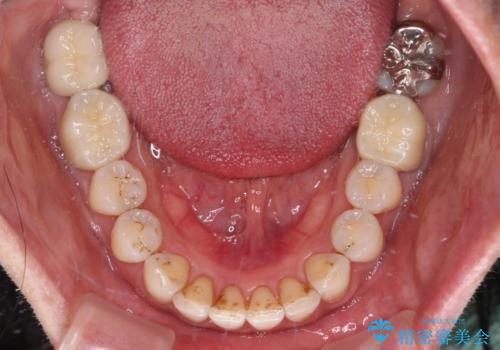

- 以前行った抜歯矯正が後戻りし、開いてしまったスペースが気になるとのことで来院された患者様です。

インビザラインを用いて開いてしまったスペースと前歯のデコボコを改善することとしました。

矯正治療後には気になっていた銀歯をセラミッククラウンやセラミックインレーにて治療することとしました。

上顎前歯を左右対称となるように歯列を整えたいとのことでしたが、すり減って形態が大きく異なっていたため、できる範囲での仕上がりとなりました。